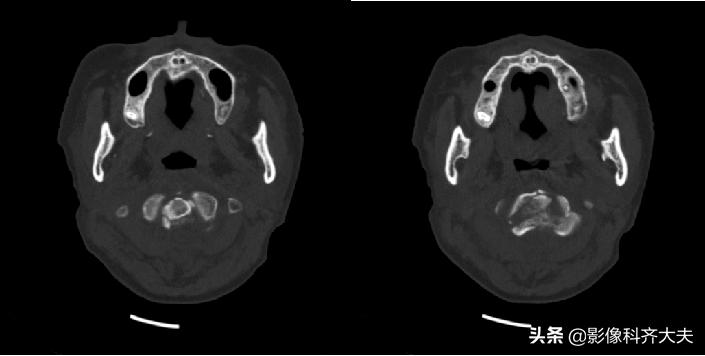

枢椎骨折

枢椎骨折矢状面重建

MRI矢状面枢椎骨折压迫脊髓

颈椎滑脱骨折脊髓挫伤